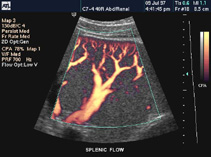

Triplex Αγγείων-Ήπατος- χοληφόρων - παγκρέατος -σπληνός -Νεφρών- κύστεως- προστάτου-Έσω γεννητικών οργάνων - κυήσεως-Επιφανειακών οργάνων-Μαστών-Θυρεοειδούς αδένος - Όσχεου- Αρθρώσεων